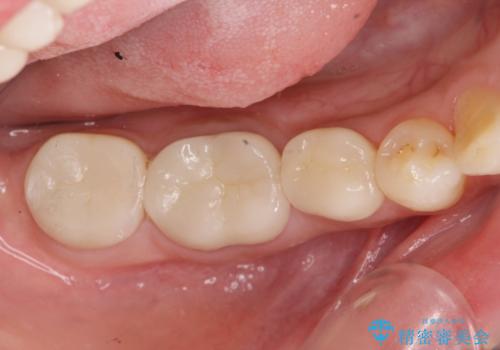

- 治療途中で放置してしまった奥歯の治療の続きを希望され来院されました。

奥歯は既に根管治療が為されクラウンを装着する必要性がある状態ですが、歯の高さが低くクラウンの安定性・強度を担保するために歯周外科を行う治療計画としました。

歯周外科を行うことで、歯ぐきの位置を下げ歯の高さを作り出し安定したクラウンの装着が可能となります。また同時に舌の邪魔となっていた骨隆起の除去を行うこととしました。